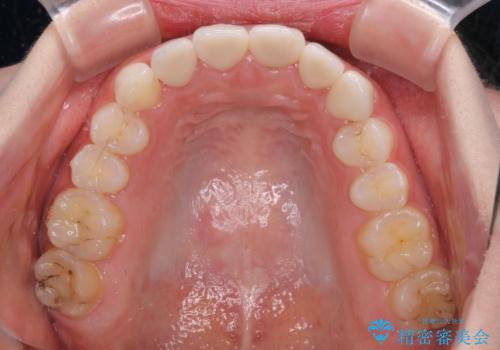

上下前歯の歯列不正はインビザラインにより歯列を整え、その後に、前歯5本をオールセラミッククラウンにて補綴治療することとしました。

矯正治療にて歯並びを整えた後に、虫歯の大きかった5本の歯をセラミッククラウンにて補綴し、明るい口元になりました。